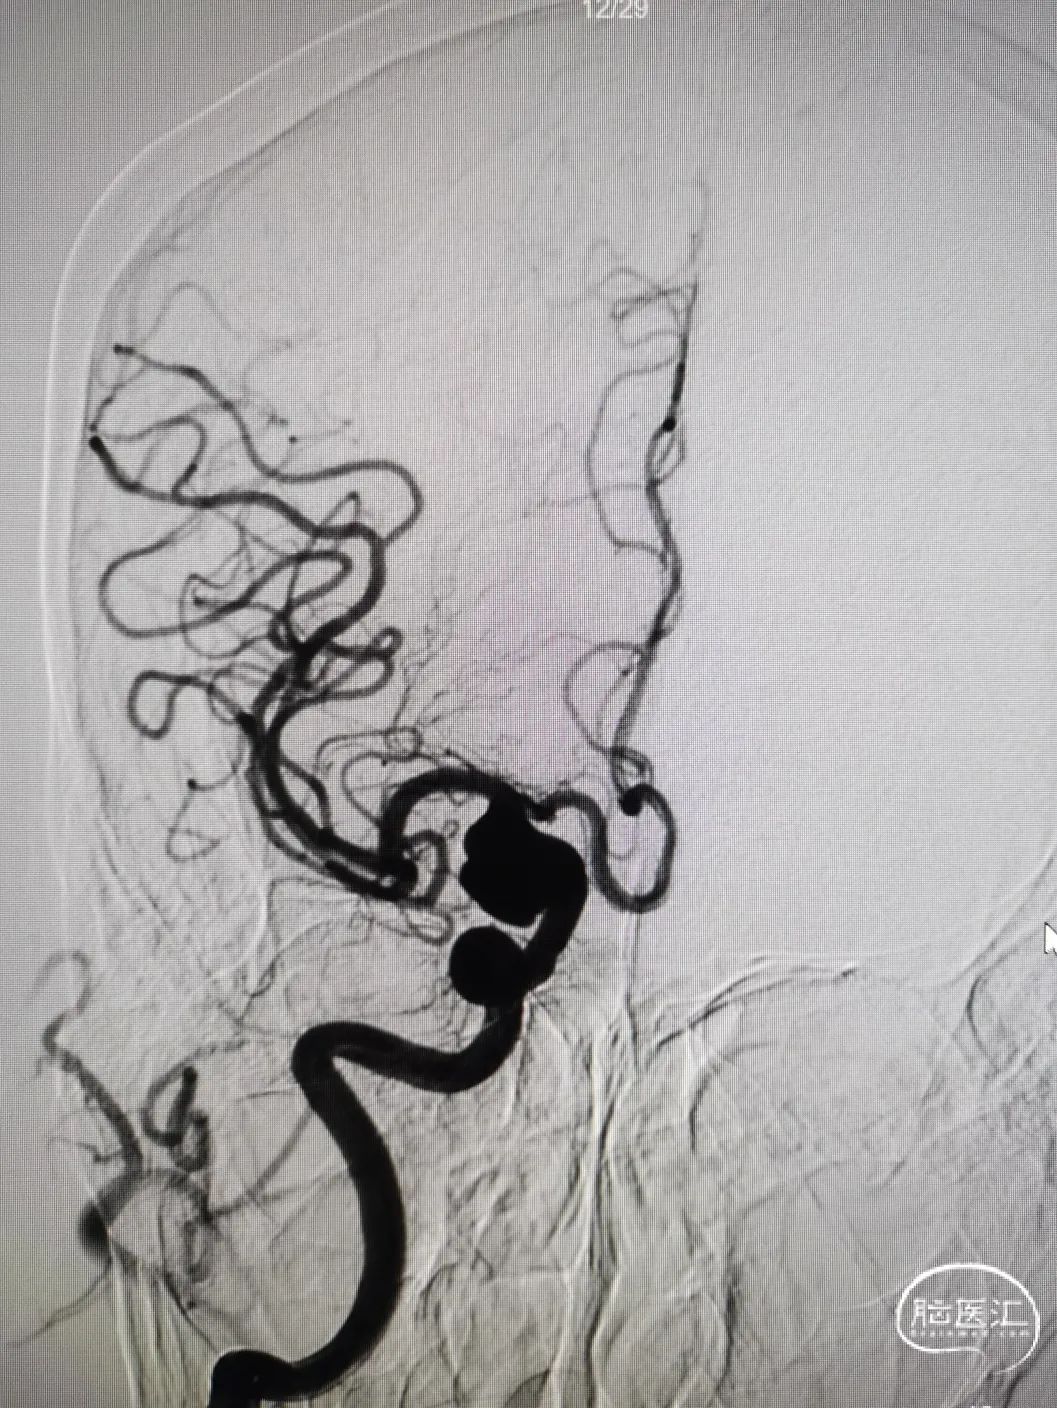

图4右颈内动脉海绵窦段起始部类圆形瘤样扩张,最大约19mm╳14mm,瘤颈约14mm,瘤内射流明显,载瘤动脉远端5mm,近端4.5mm。

8F常规指引到右颈内动脉开口做近端支撑。Synchro 0.014 200微导丝及XT-27微导管引导CAT 5导管同轴越过右颈内动脉瘤至右大脑中动脉M1。由于动脉瘤颈较大,微导丝引导XT-27微导管,无法直接通过,采用瘤内成袢技术通过。选取Surpass Streamline 5mm╳30mm经CAT 5导管释放,并行微导丝及CAT 5导管按摩。

图5